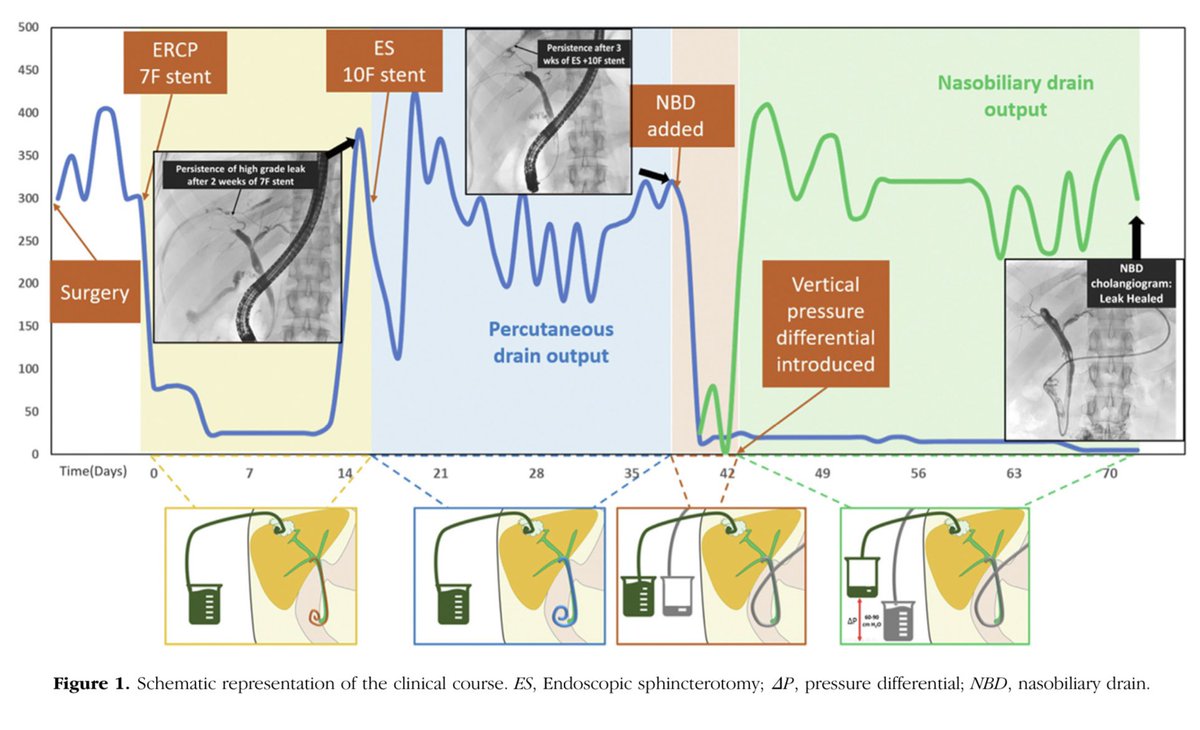

Hoy toca cerrar una etapa, muchas gracias Digestivo Hospital Universitario Ramón y Cajal por estos meses de aprendizaje. #CPRE